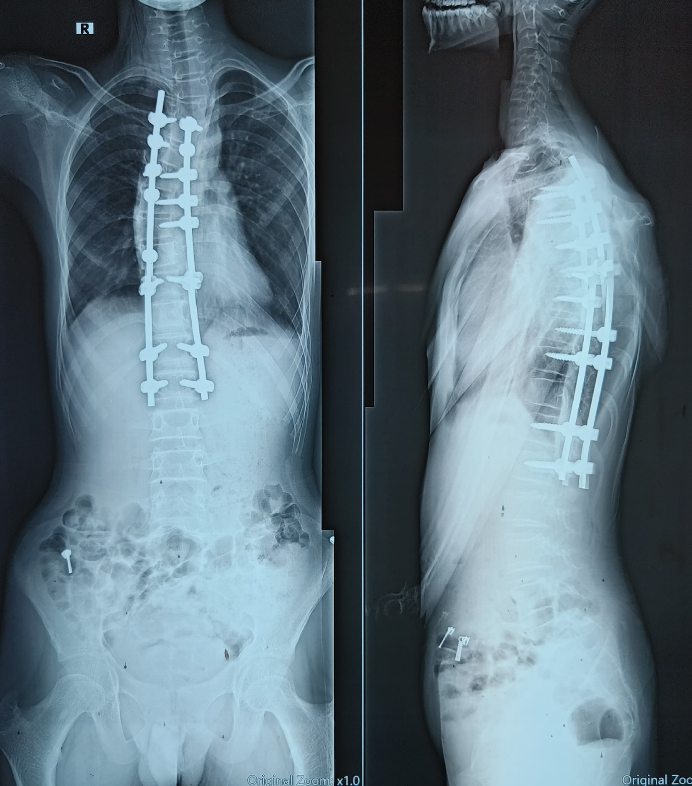

Patient underwent D5 – D10 laminectomy, posterior midline myelotomy and near total tumor resection along with instrumentation from D4 to L1 was done for deformity correction under neuromonitoring (Fig. 4 and 5). Intraoperatively, greyish yellow, non-friable, firm, and poorly differentiated tumor tissue was noted. In view of possible iatrogenic neurological deficits and poorly differentiated tumor, complete resection could not be achieved. Histopathological reports were suggestive of low-grade glioneuronal tumor compatible with ganglioglioma (Fig. 6). As the tumor was of Grade 1 WHO, adjuvant chemotherapy or radiotherapy was not indicated. Post-operative physiotherapy for posture and gait correction was initiated. In due course of follow-up at 6 months, 1 year, and 2 years, patient was comfortable, pain had reduced, his posture had improved, and there were no new-onset neurological deficits.

Figure 5: Post-operative X-ray.